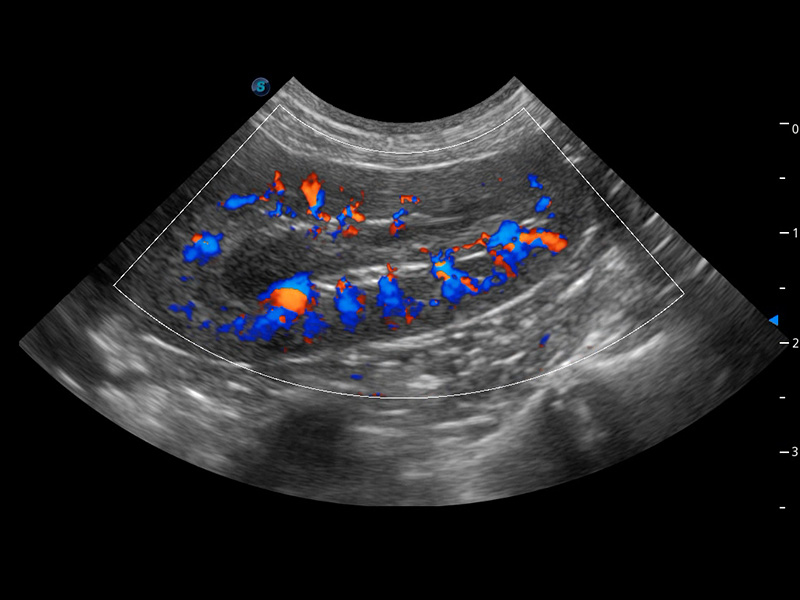

ProPet 60 作为一款高端台式动物超声设备,为动物医生的日常诊断提供了一系列贴合动物临床需求、解决临床实际问题的高级成像功能。凭借全系列高清探头,满足医生对腹部、心脏、生殖、浅表、肌骨等成像的所有需求,切实帮助您提升检查效率,提高诊断信心。

动物是人类最亲密的朋友和最值得信赖的伙伴。DB中国旗舰官方网站也一直致力于探索动物专用的超声影像解决方案。 全新推出的ProPet系列,是DB中国旗舰官方网站在动物超声影像智能化、专业化、精准化的一次跨越式革新。动物不能用言语来表述自己的不适,通过超声影像,ProPet系列搭建了动物医生与不同物种沟通的“桥梁”,为动物医生注入了“治愈之力”。